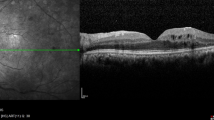

Because ranibizumab and aflibercept are approved in Japan and bevacizumab is not, we used these two approved anti-VEGF agents for the DME treatment. The inclusion criteria were; (1) patients ≥20-years with type I or type II diabetes, (2) eyes with DR and DME and the diagnosis of DME was made by the clinical and spectral domain optical coherence tomographic (SD-OCT) findings, (3) DME involving the fovea and defined as a central macular thickness (CMT) ≥300 µm measured as the mean retinal thickness in the central 1 mm diameter circle in the OCT images.